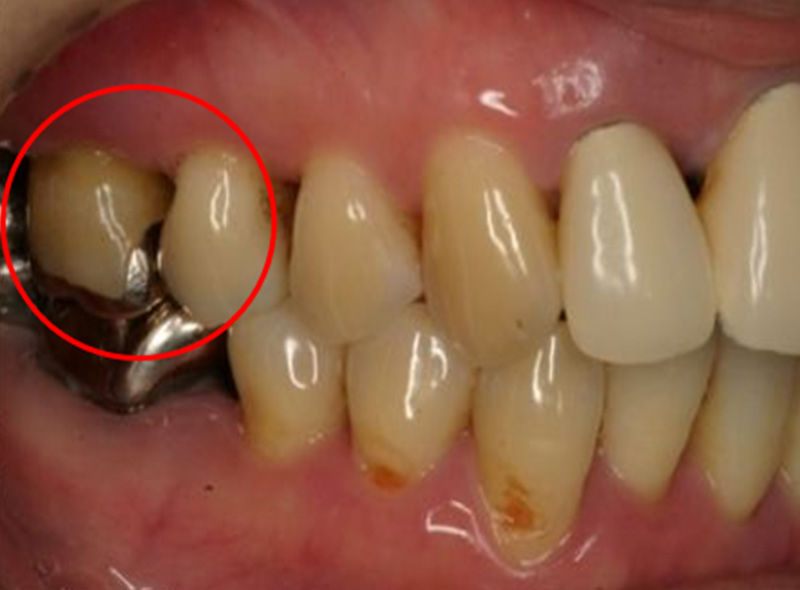

根分岐部病変

(根が分岐している奥歯に生じた歯周病)

の治療

~専門医・指導医による歯周病治療3~

治療の概要

根分岐部病変は、歯根が2本以上ある歯の根分岐部まで進行した歯周病で、歯石除去が難しくブラッシングもしにくい場所のため、症状が出にくく治療が難しいのが特徴です。歯周病を制するには根分岐部病変を制する必要があり、進行した場合は抜歯の選択肢が検討されることも少なくありません。

さっさと抜いてインプラント、ではなく、根分岐部病変をどう考えてどう生かすかが歯周病専門医の姿勢や力量です。

治療例の紹介